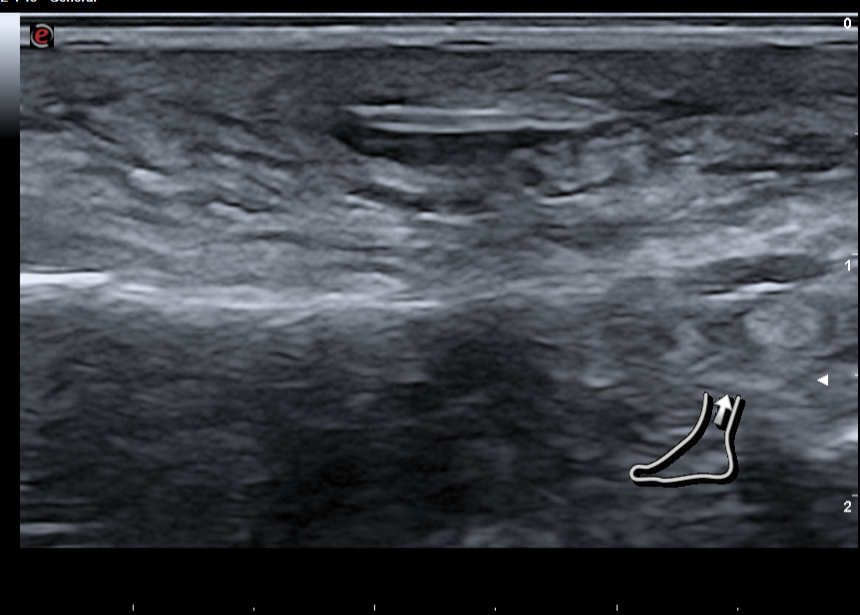

Decido realizar ecografía en cara lateral del tobillo izquierdo.

Hallazgos ecográficos

En la ecografía con sonda lineal, se aprecia material hiperecogénico de 5 mm en diámetro longitudinal en tejido subcutáneo, sin sombra acústica, con reborde anecogénico, a 4 mm de superficie de piel y signos de empedrado en tejido subutáneo. Compatible con cuerpo extraño en tejido subcutáneo con celulitis asociada.